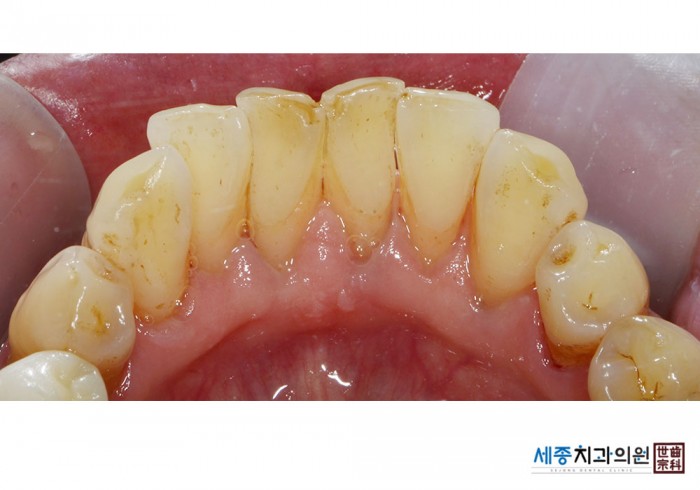

[스케일링] 치주질환 예방 스케일링

치료전 : 2020-03-18

가글마취&저주파 스켈러를 사용한 착색제거 스케일링